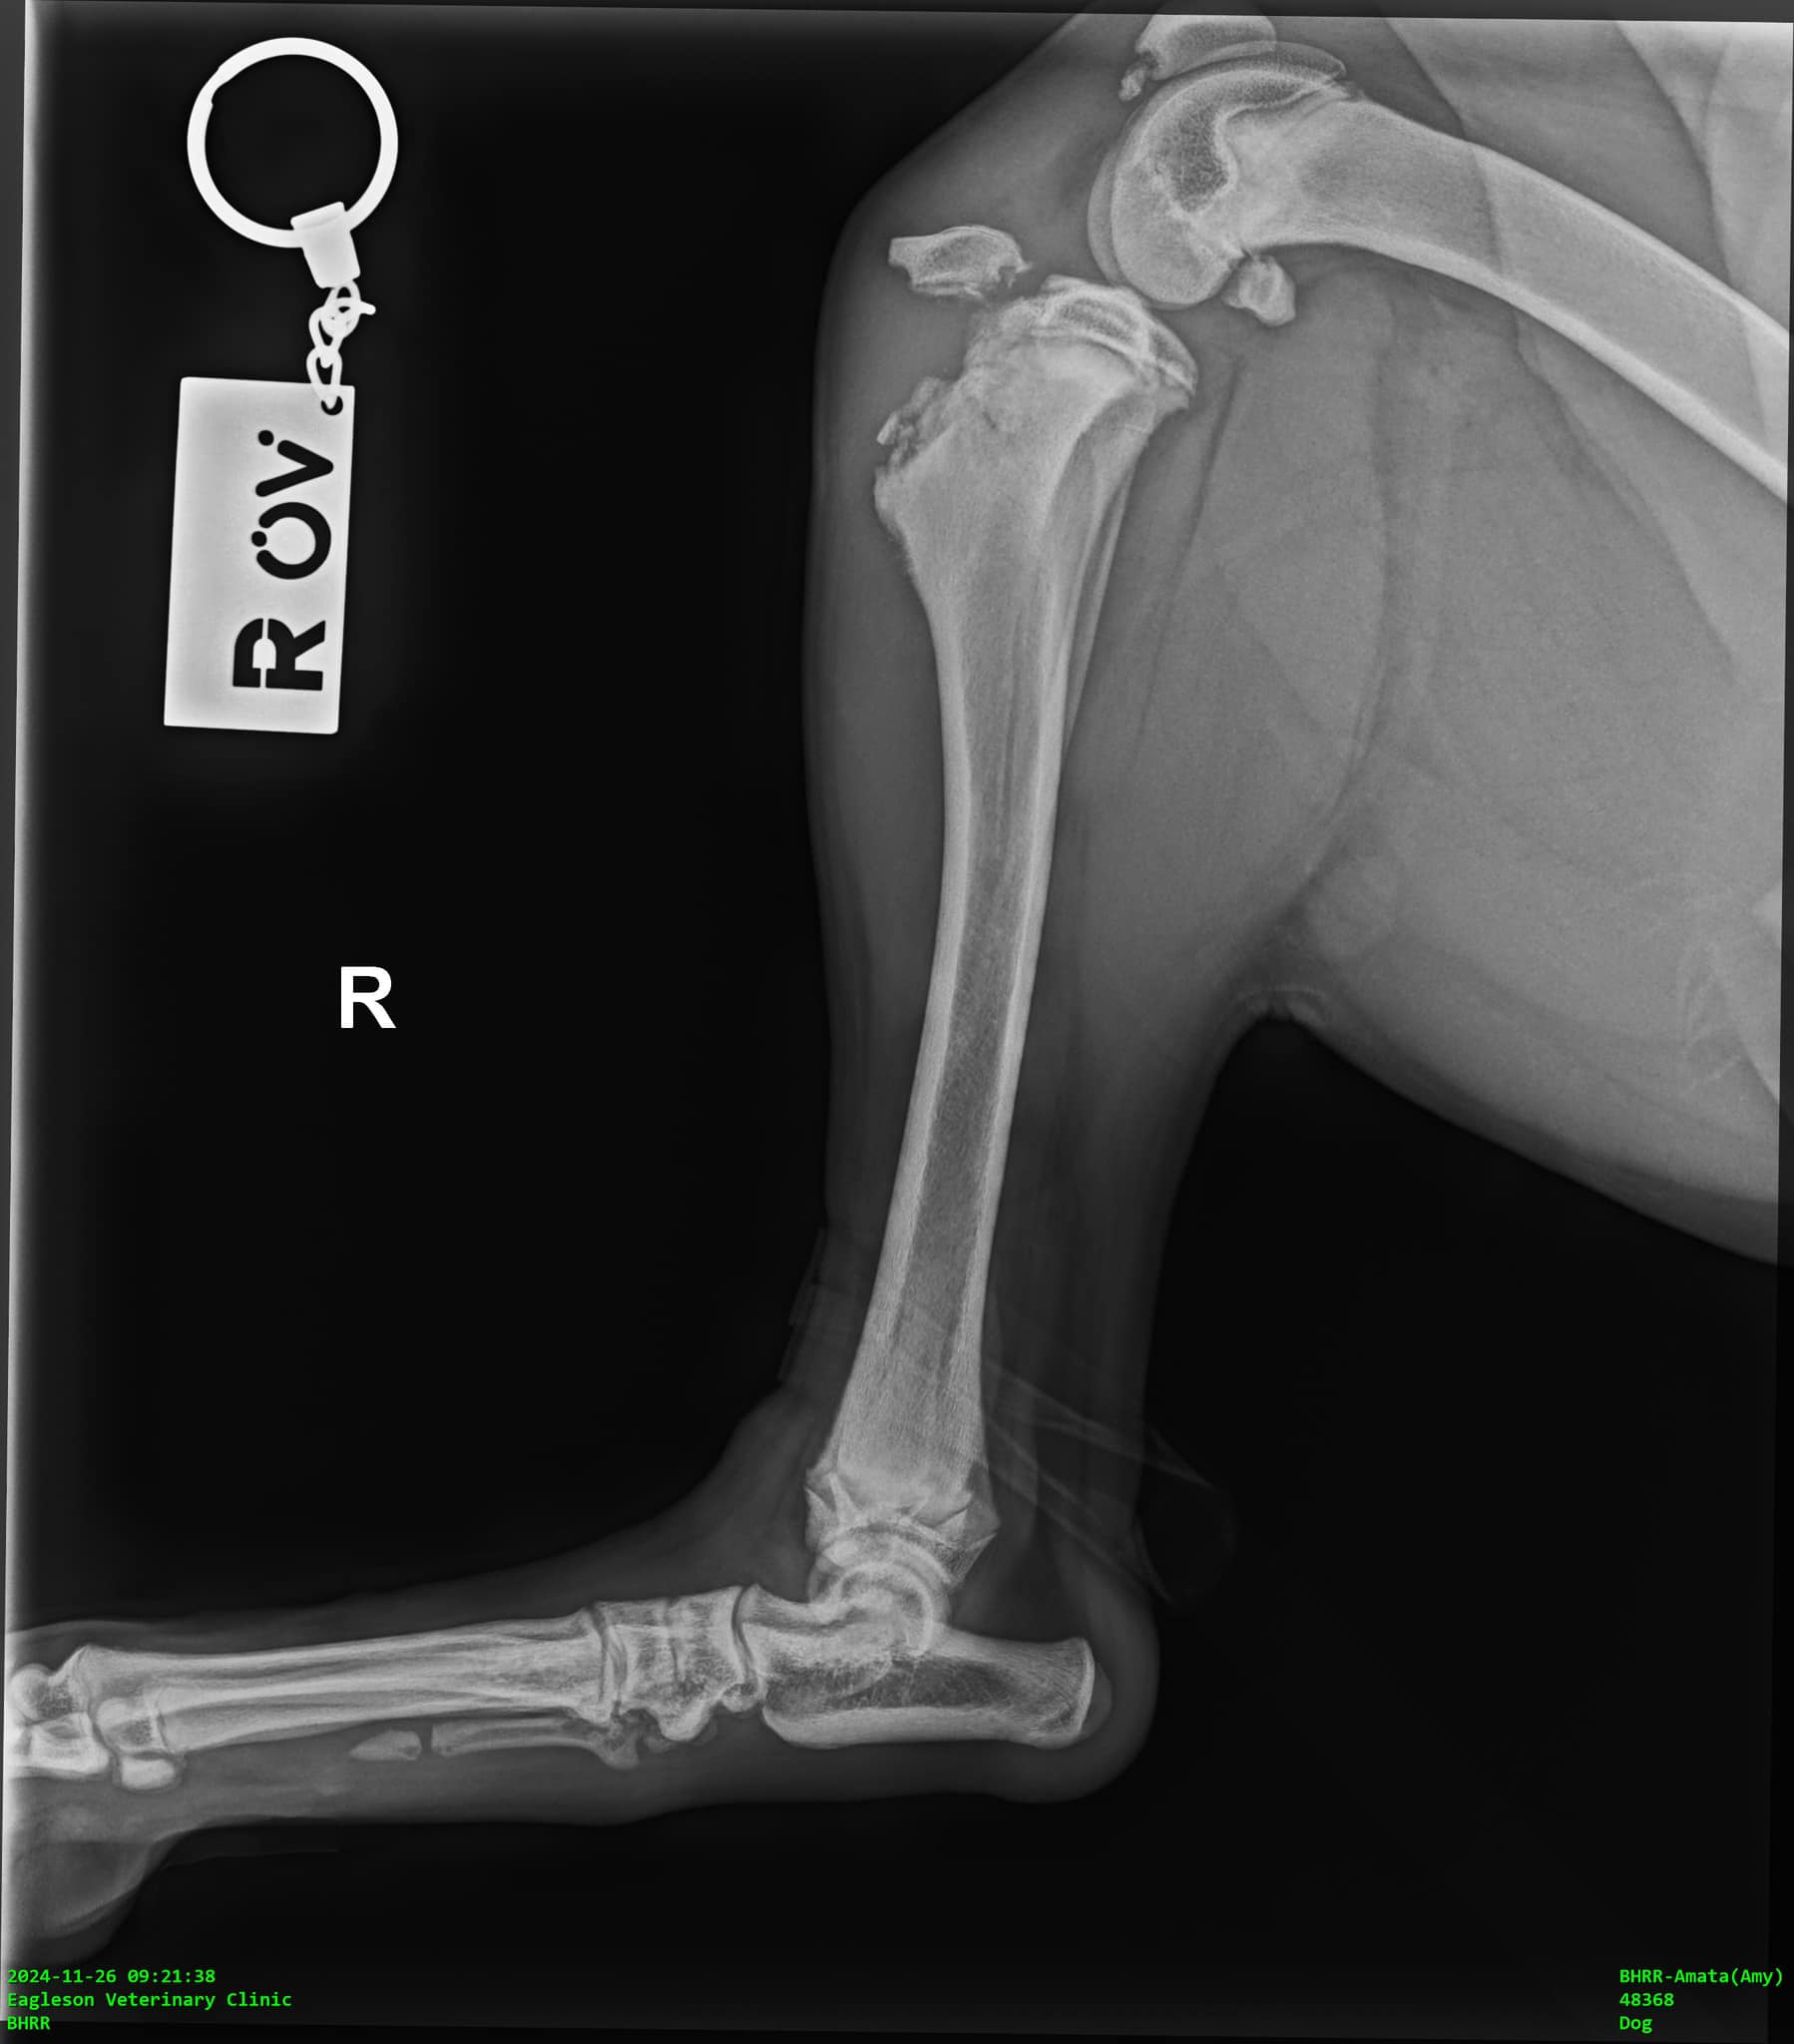

Miss Amy’s back right leg x-ray November 26th, 2024.

We did both shoulders too and her other leg for comparison. She has now had three rounds of x-rays to monitor closely the changes and to ensure that she has no missed injuries.

Three ortho specialists have assured me that it is ONLY her back right leg that is broken, and that he back left is perfectly normal for a young large breed puppy.